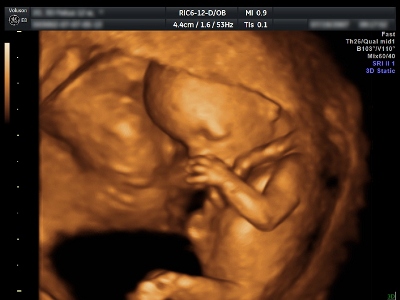

La Cassazione rispolvera il danno esistenziale. Va risarcito anche il padre del bambino nato con una malformazione non diagnosticata dalla struttura sanitaria in tempo per far decidere alla madre se abortire o meno.

Senza riaffermare esplicitamente l’esistenza del danno esistenziale la Suprema corte, in un passaggio della sentenza n. 13 del 5 gennaio 2010, lo ripropone di fatto come modello risarcitorio, non sapendo come altro riconoscere il ristoro al danno indiretto sofferto da un padre di un bambino nato malato e al quale era senz’altro cambiata tutta l’esistenza. “La nascita indesiderata determina – mettono nero su bianco gli Ermellini – una radicale trasformazione delle prospettive di vita dei genitori, i quali si trovavano esposti a dover misurare (non i propri specifici valori costituzionalmente protetti, ma) la propria vita quotidiana, l’esistenza concreta, con le prevalenti esigenze del nascituro, con tutti gli ovvi sacrifici che ne conseguono”. Quindi, continuano i giudici con un documento che è destinato a sollevare antiche polemiche fra studiosi e magistrati, “le conseguenze della lesione del diritto di autodeterminazione nella scelta procreativa, allora finiscono per c onsistere proprio nei rovesciamenti forzati dell’agenda di cui parte della dottrina discorre nel prospettare la definizione del danno esistenziale. Insomma, tale caso sembra costituire un caso paradigmatico di lesione di un interesse che non determina un prevalente danno morale o biologico, peraltro sempre possibile, ma impone al danneggiato di condurre giorno per giorno, nelle occasioni più minute come in quelle piú importanti, una vita diversa e peggiore di quella che avrebbe altrimenti condotto. In casi del genere, il danno risarcibile non può essere limitato solo al danno alla salute in senso stretto della gestante”.